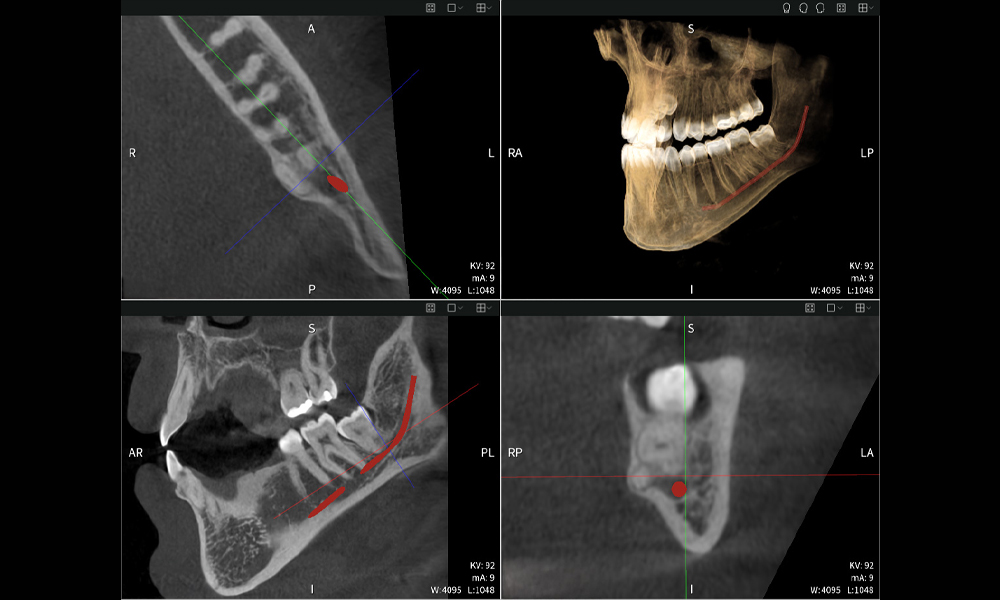

Figures b–d show various views of a 3D reconstruction of the mandible, providing a comprehensive overview of the mandibular anatomy, the position of the nerves in relation to the teeth, and allowing assessment of tooth symmetry and alignment.

Figure d shows the previously treated tooth 48, with its crown removed, and its roots left in proximity to the nerve, illustrating the high risk of nerve damage.

Figure e: The panoramic X-ray serves as an initial assessment tool, showing the general positioning of the teeth as well as any potential pathological changes. Notably, on the right side (tooth 48), the situation following a crown amputation performed by an external practitioner is visible. The two severely curved roots remain in close topographical proximity to the inferior alveolar nerve within the bone. This suggests a deliberate decision to avoid the increased risk of nerve injury during a complete extraction, and represents a clinically relevant finding. In summary, CBCT scans with Seethrough Max, provide crucial information about the complex anatomy and the critical relationship between the wisdom teeth and the inferior alveolar nerve. This detailed preoperative diagnostic imaging is essential for safe and successful surgical procedures in the mandibular region.